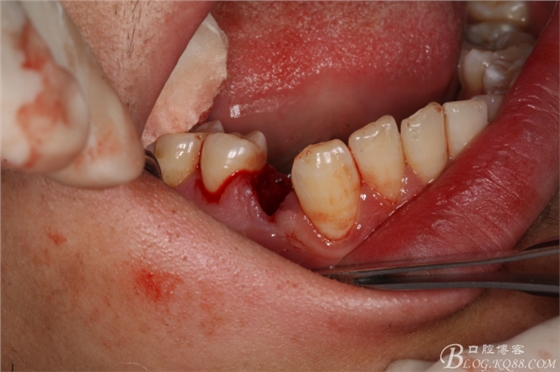

圖4.患者的口內(nèi)影像檢查:右側(cè)47萌出少,合向脫位間隙亞種不足

圖5.左側(cè)37萌出較多、合向脫位間隙依然不足